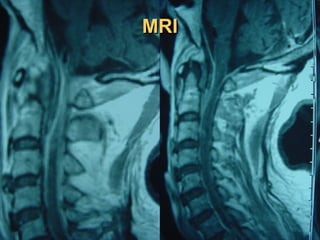

Spinal MRI is the procedure of choice

(sensitivity 95%, specificity 92%).

Gadolinium enhancement increases sensitivity

and enables better differentiation between

abscess and surrounding neurological

structures.

MRIMRI